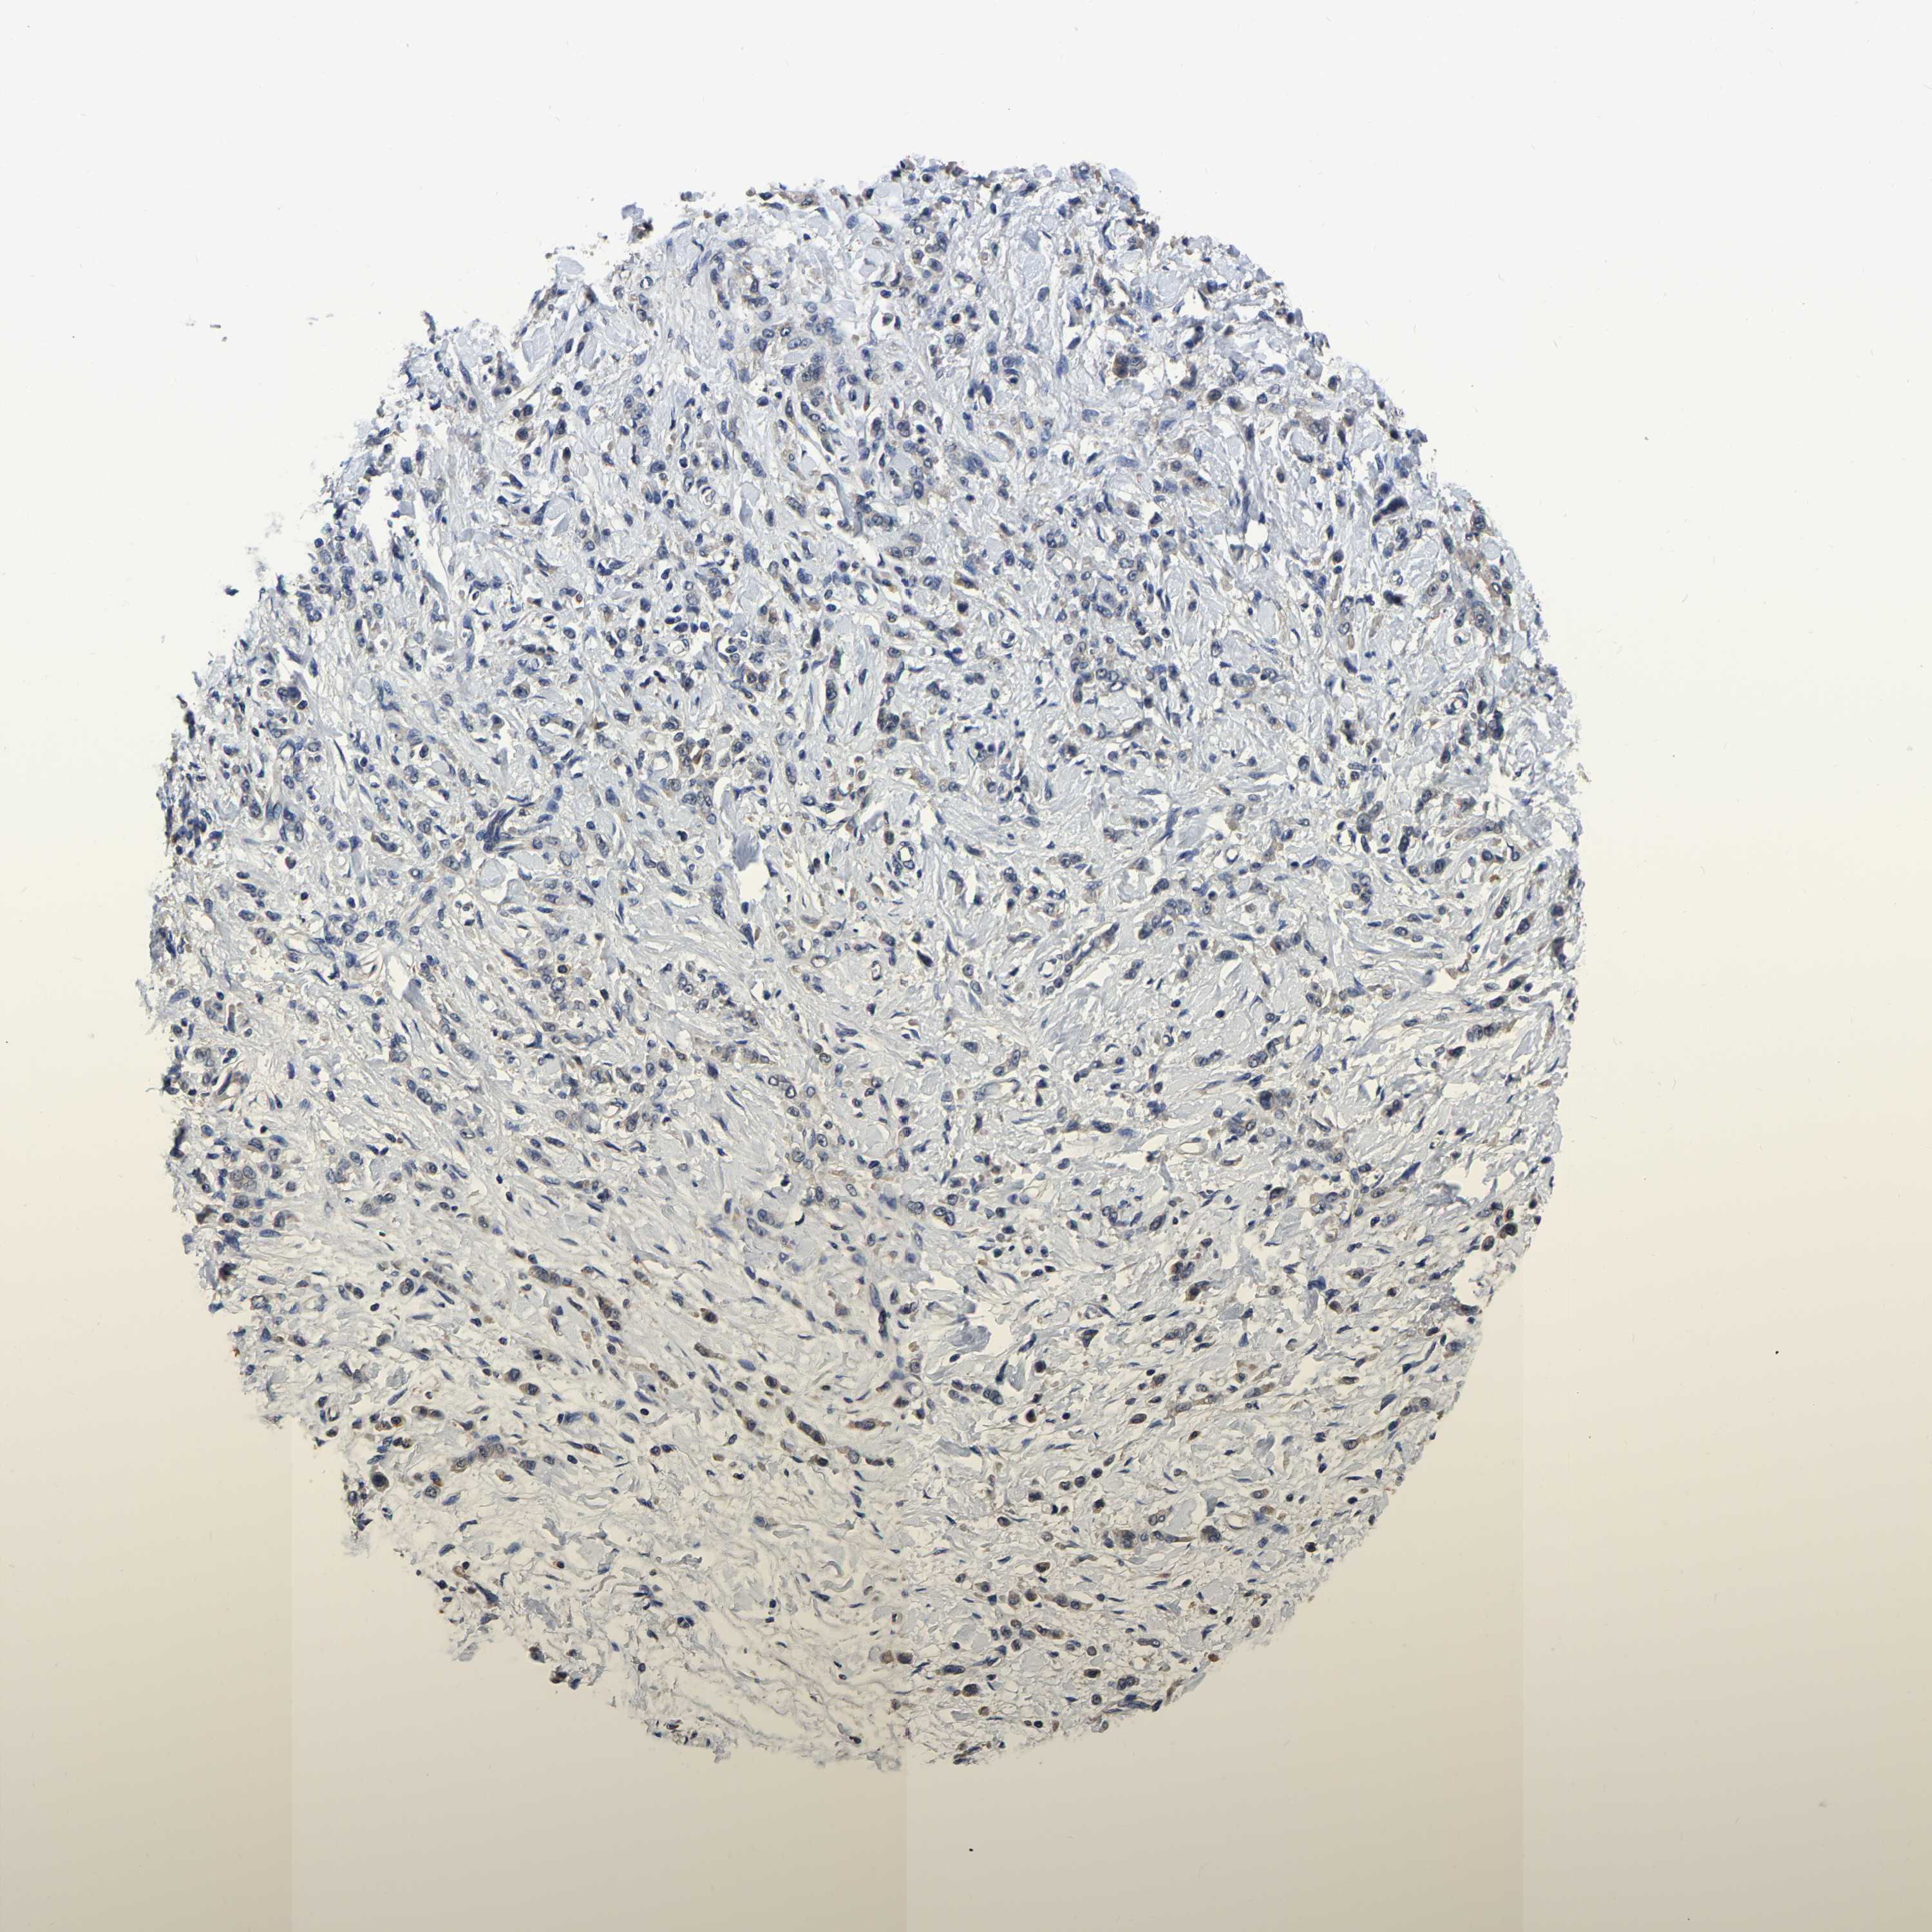

STOMACH CANCER - Protein expressioni

A mouse-over function shows sample information and annotation data. Click on an image to view it in a full screen mode. Samples can be filtered based on level of antibody staining by selecting one or several of the following categories: high, medium, low and not detected. The assay and annotation is described here.

Note that samples used for immunohistochemistry by the Human Protein Atlas do not correspond to samples in the TCGA dataset.

Antibody stainingi

Antibody staining in the annotated cell types in the current human tissue is reported as not detected, low, medium, or high, based on conventional immunohistochemistry profiling in selected tissues. This score is based on the combination of the staining intensity and fraction of stained cells.

Each image is clickable and will lead to virtual microscopy that enables deeper exploration of all samples and also displays staining intensity scores, fraction scores and subcellular localization as well as patient and tissue information for each sample.

Antibody HPA017894

Staining

High

Medium

Low

Not detected

Intensity

Strong

Moderate

Weak

Negative

Quantity

>75%

75%-25%

<25%

None

Location

Nuclear

Cytoplasmic/membranous

Cytoplasmic/membranous,nuclear

Adenocarcinoma, NOS